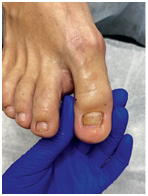

Иллюстрация к книге — Подология понятно. Важен каждый шаг. Справочник по проблемам подологии для клиентов и мастеров эстетики [i_274.jpg]

Иллюстрация к книге — Подология понятно. Важен каждый шаг. Справочник по проблемам подологии для клиентов и мастеров эстетики [i_275.jpg]

Иллюстрация к книге — Подология понятно. Важен каждый шаг. Справочник по проблемам подологии для клиентов и мастеров эстетики [i_276.jpg]

Клиент обратился с проблемой отрастания здорового ногтя, был отправлен на консультацию к хирургу на предмет экзостоза. Диагноз подтвердился, была проведена операция, и спустя месяц клиент обратился к нам за помощью в отращивании здоровой ногтевой пластины